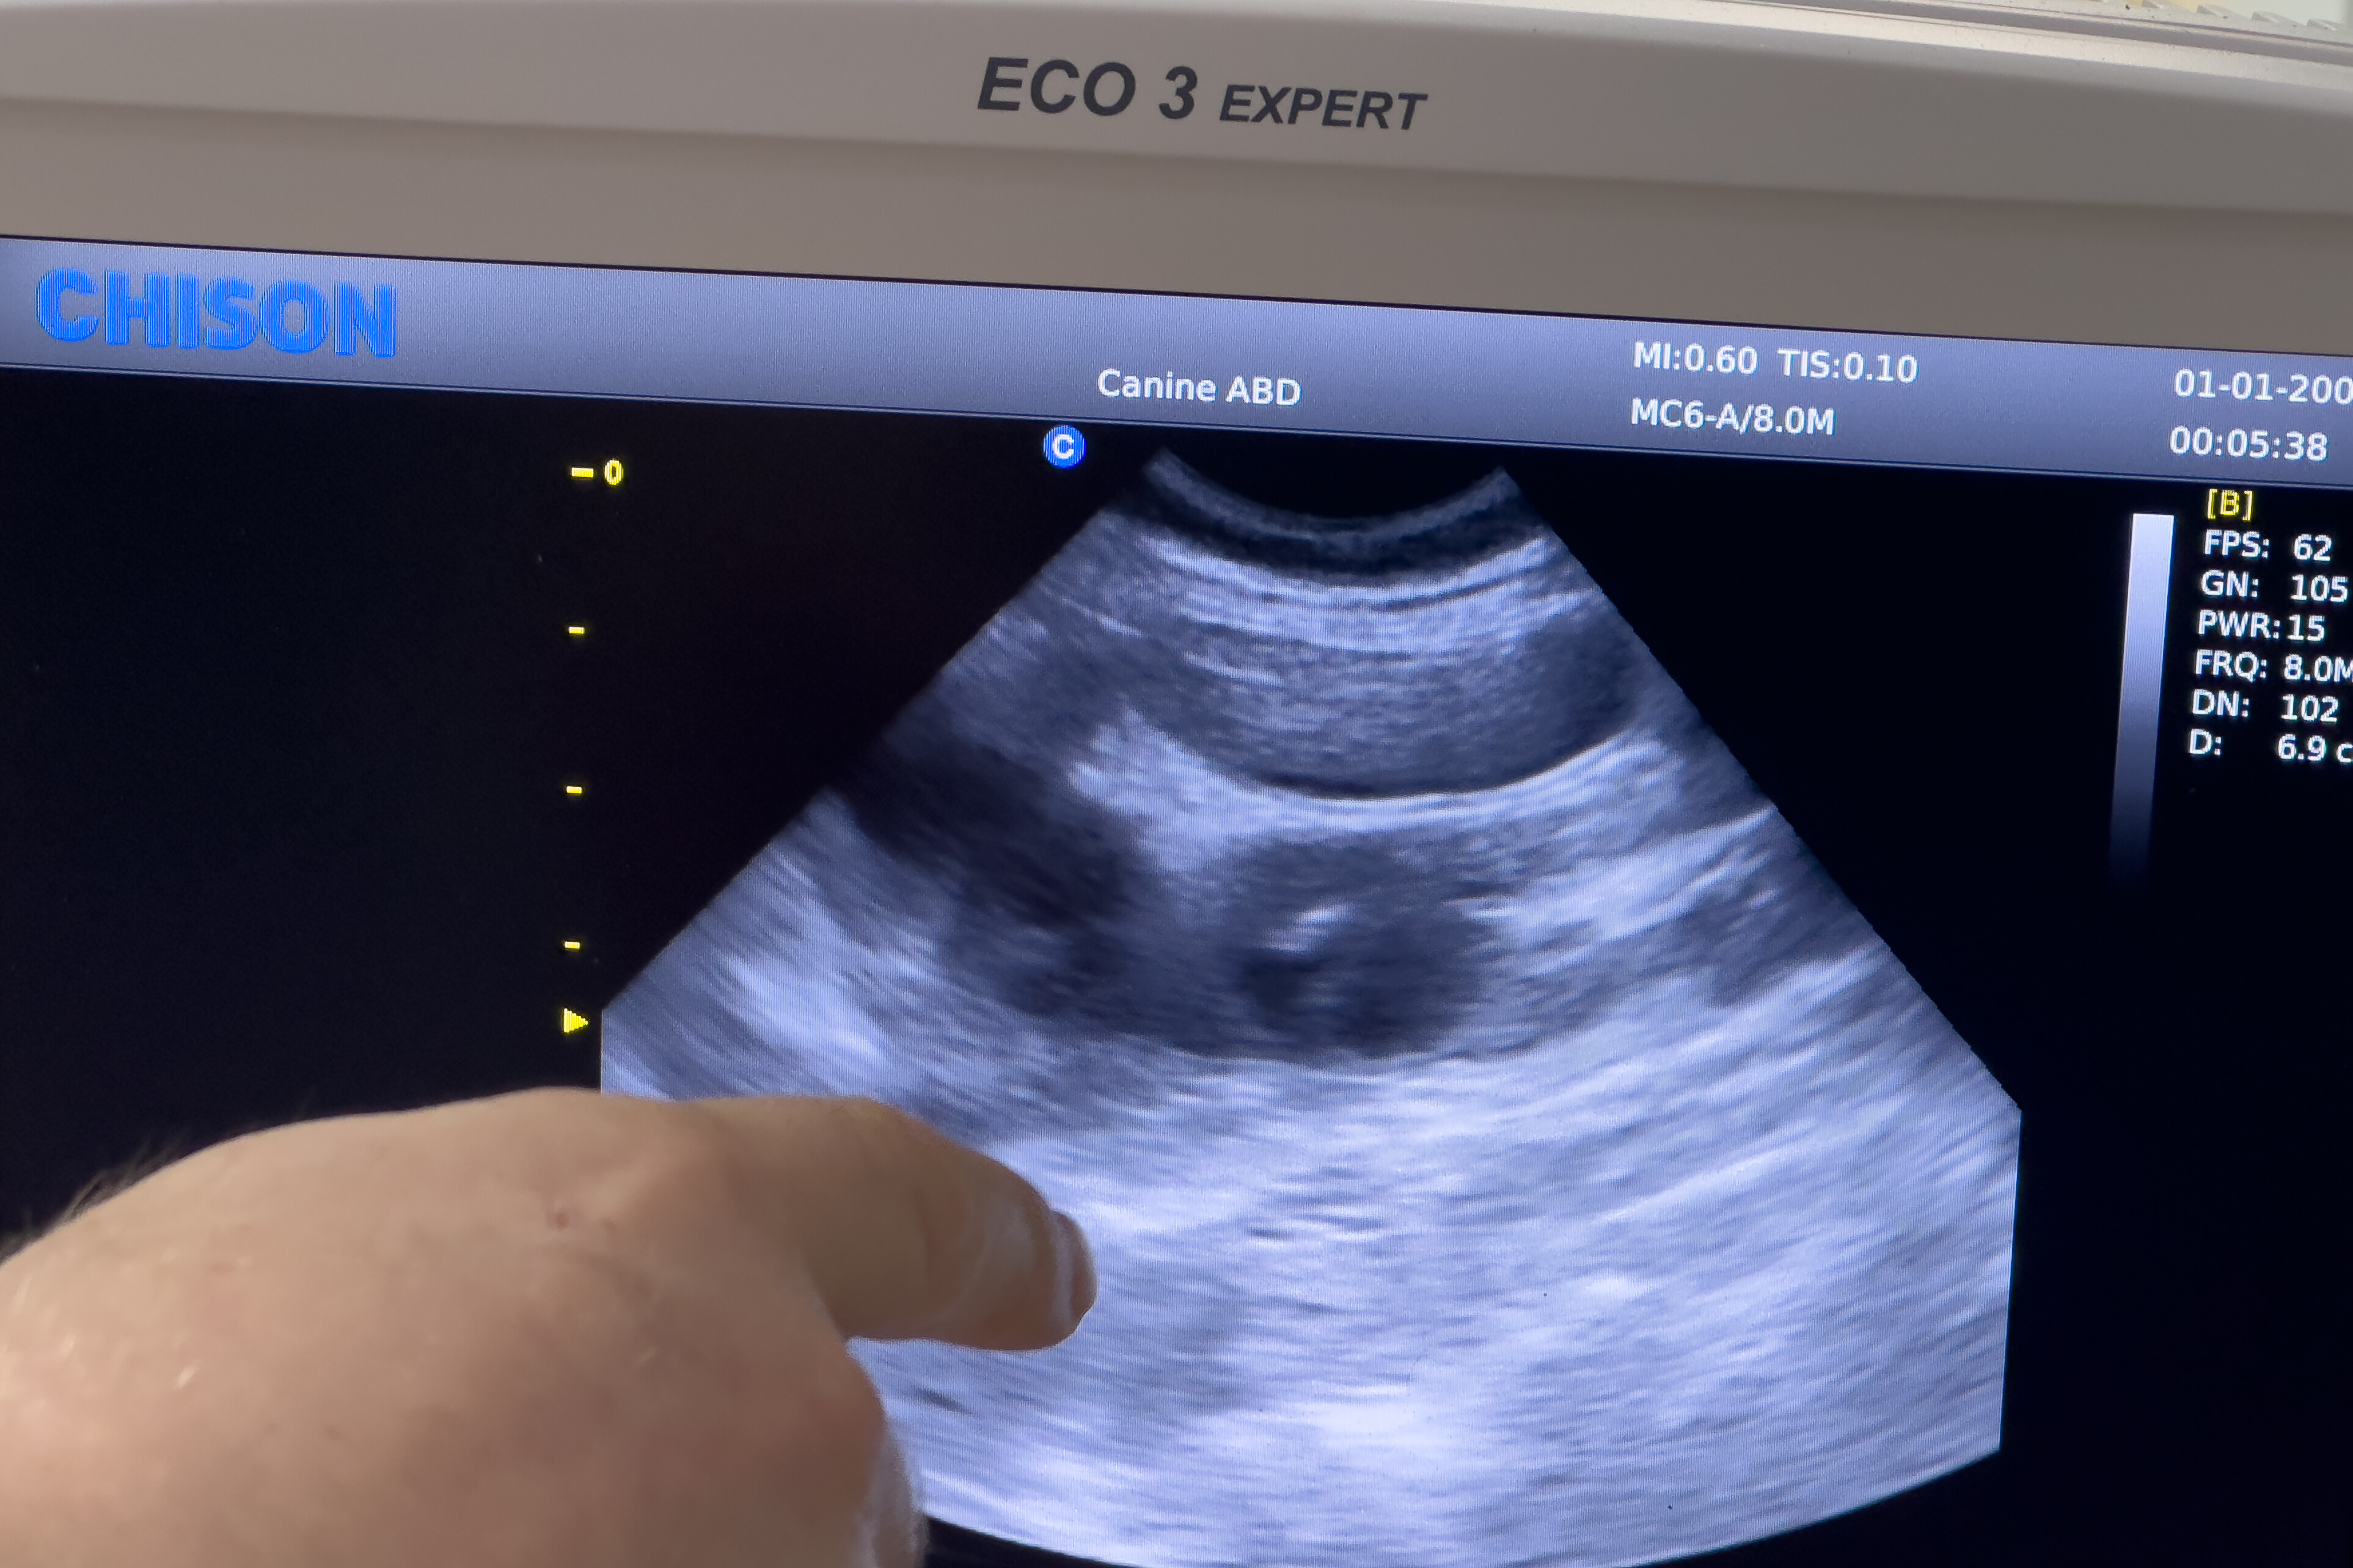

Еще за пару недель до этих фотографий мы сходили к ветеринару сделать US и посмотреть что же носит в себе наша корги. Результат нас ошарашил… Вот вы сколько щенков видите? И я ни одного….